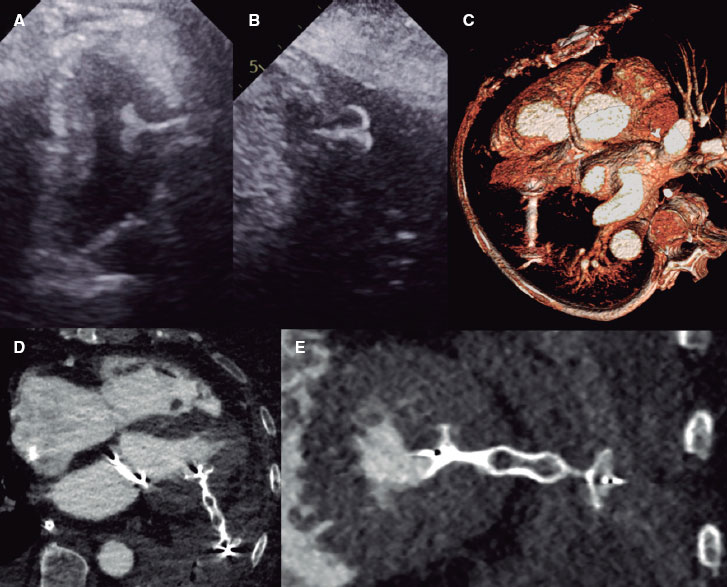

To fulfill the needs of computational processing and modeling in interventional cardiology, various new technologies are being developed that leverage the rich data available from intravascular imaging. The detection and measurement of geometric features is already available in limited cases, and it is likely to expand. The automated delineation of the lumen and external elastic lamina is incorporated in some intravascular ultrasound systems, and developments in computational processing have recently yielded promising results to identify these, as well as the internal elastic lamina, in optical coherence tomography images. Facilitated by automated detection of inner and outer vessel borders, automatic measurements from pullbacks such as lumen area, plaque burden, eccentricity, and remodeling index will reduce the need for manual identification and annotation of the most critical frames and will enable better visualization of diseased vessels. This information may also be used, for example, in the proper sizing of balloons and stents.

Advances in image processing also offer improved availability of information on lesion morphology. While experts are generally adept at determining the composition and distribution of plaque from cross-sectional images, doing so is a slow process that requires extensive expertise. Increased availability of automated virtual histology will improve the characterization, profiling, and stratification of lesion phenotypes. New image-based methods to characterize the stiffness of diseased tissue also promise greater insight into the mechanical profile of a lesion. Altogether, this information on plaque distribution and properties will help cardiologists to plan and guide interventions (eg, by informing the need for lesion preparation or modification prior to ballooning or stenting).